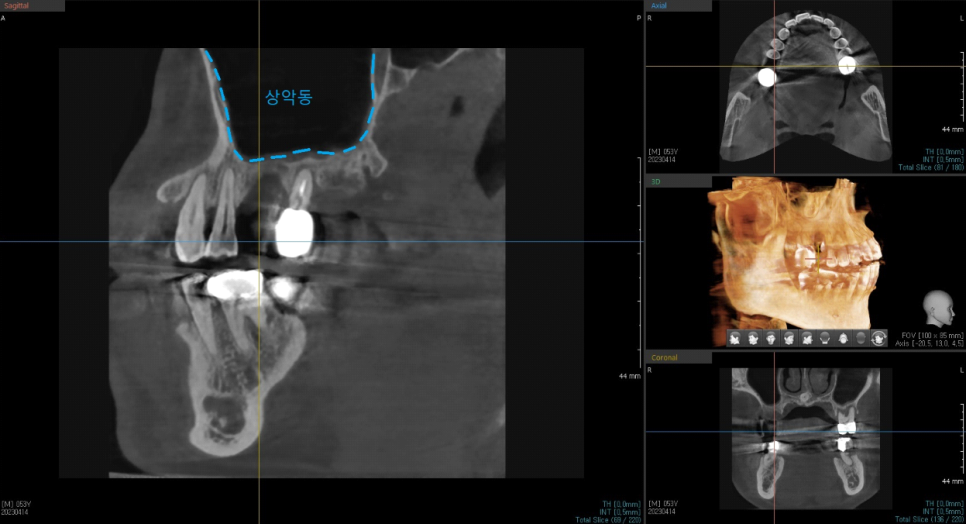

상악 임플란트의 경우 상악동이라는 공기주머니가 얇은 막으로 둘러싸고 있는데요

상악동을 다치게 하지 않으면서 임플란트를 잘 식립을 해야 합니다.

정확하고 안전하게 임플란트를 식립을 하기 위해

네비게이션 장치 제작을 위한 CT촬영과 구강내 scan을 하여

환자분이 수술 하시기전

제가 직접 자료를 통해 수술계획을 세워 준비를 합니다.